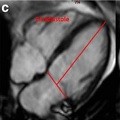

Genetic variants of HIF1α are associated with right ventricular fibrotic load in repaired tetralogy of Fallot patients: a cardiovascular magnetic resonance study

Thanh T. Hoang, et al.

Published on: 15 August 2019